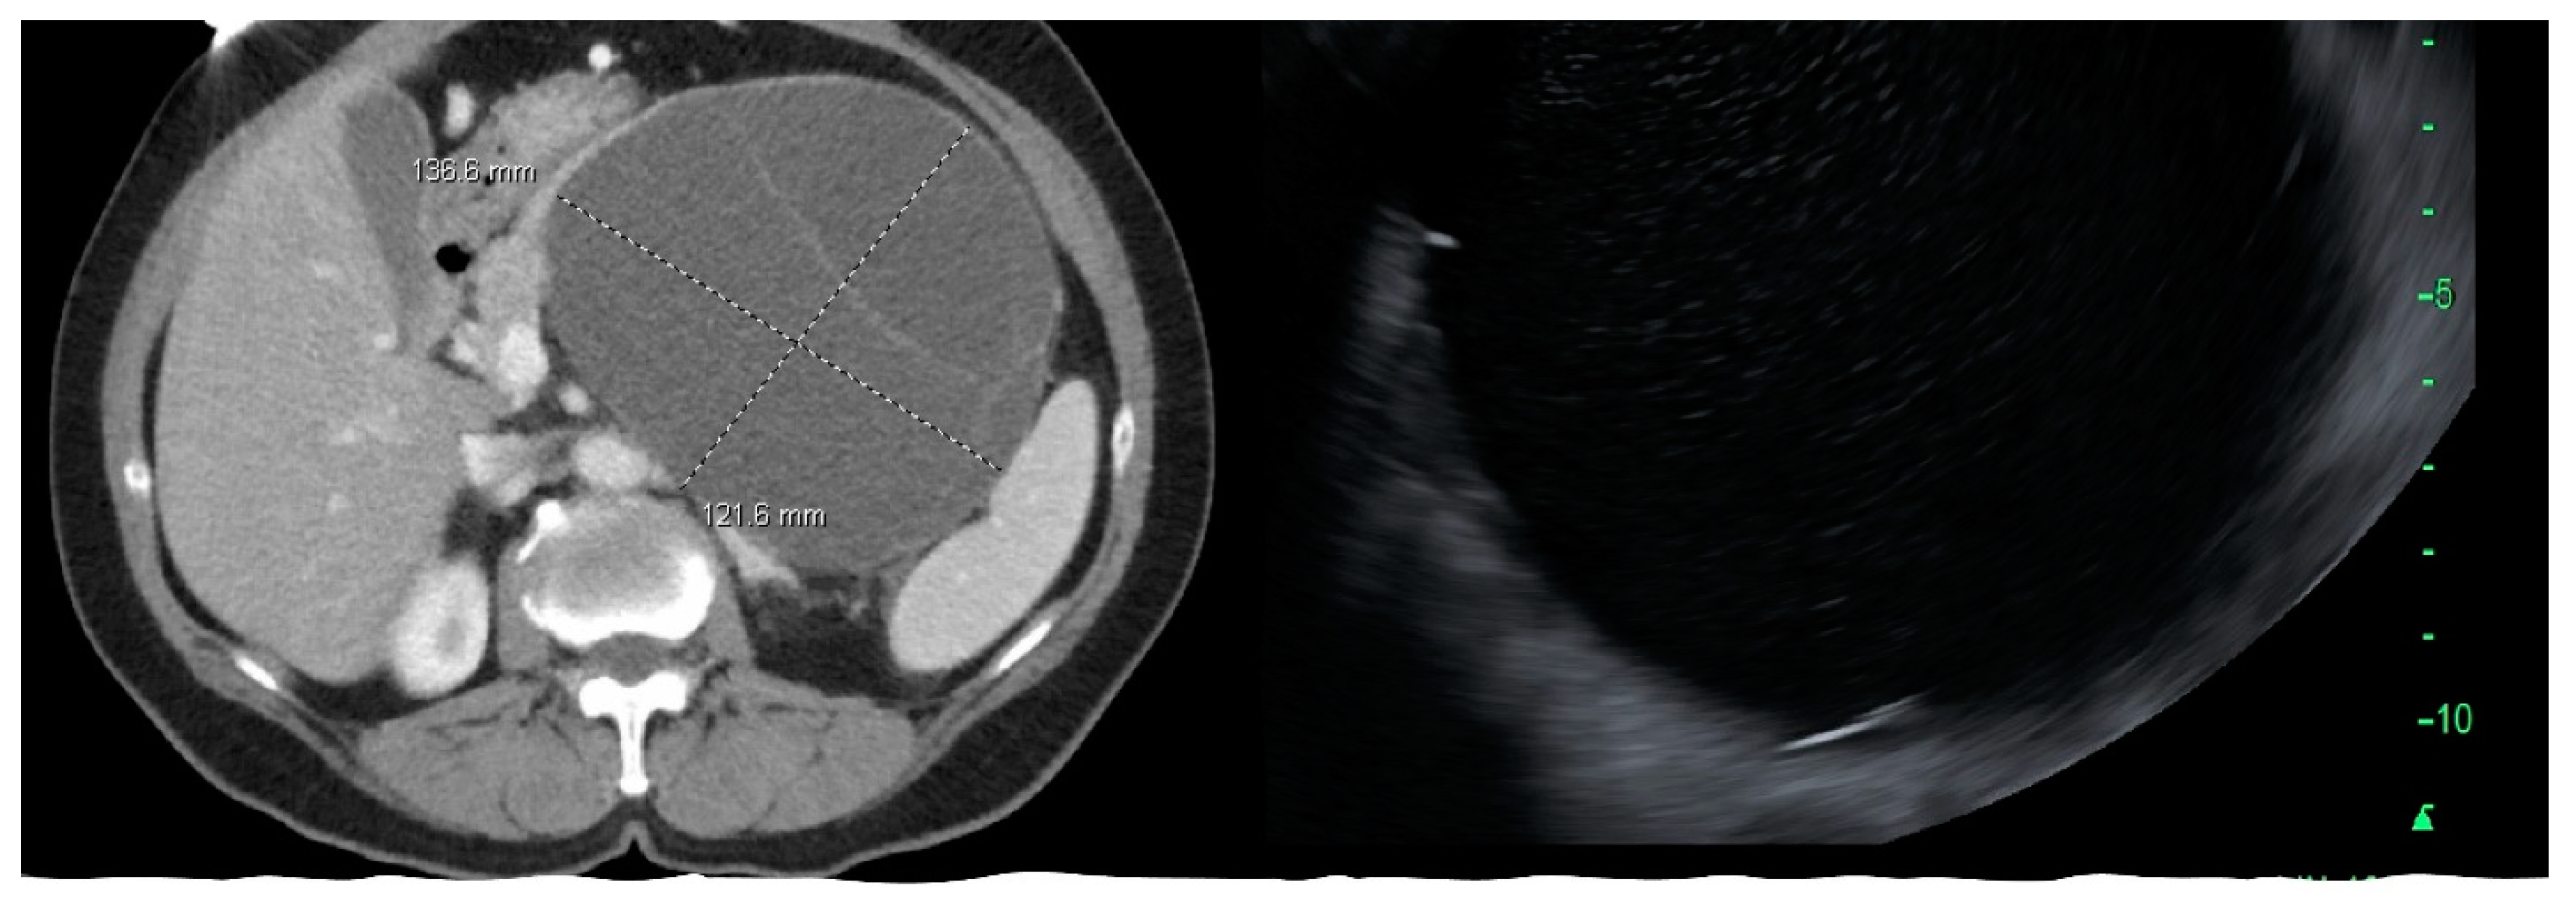

Figure 3.

CT scan and endoscopic ultrasound images of mucinous cystic neoplasm in the body and tail of pancreas.

MCN, SCA, and SPN are solitary cysts. MCN and SCA lack communication with the main pancreatic duct and do not show pancreatic duct dilation on imaging. IPMN, by definition, demonstrate communication with the pancreatic duct, have the dilation of the duct, and are commonly multiple. IPMNs are more common in the head and neck region but can be found in other locations (Figure 2). They can be multifocal and should be considered along with pseudocysts when multiple cysts occur in the pancreas. MCNs are exclusively seen in the body or tail of the pancreas (Figure 3). While SCA can occur in the head, most SCA are located in the body or tail (~70–75%). There is no specific location of SPN (Table 1).